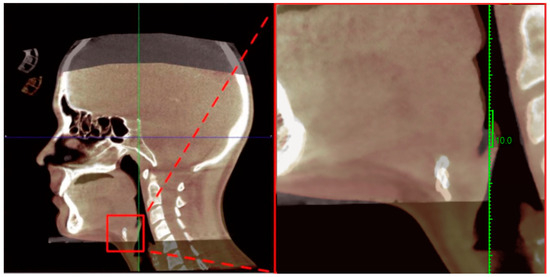

Effects of Web-Based Orofacial Myofunctional Therapy on Hyoid Bone Position in Adults with Mild to Moderate Obstructive Sleep Apnea: Evidence from an Estonian Substudy of a Randomized Controlled Trial

Background: Orofacial myofunctional therapy (OMT) is an emerging adjunctive treatment for obstructive sleep apnea (OSA), but its effects on upper airway structural support, particularly the hyoid complex, are not well defined. This study assessed the short-term effects of OMT on hyoid bone [...] Read more.

Background: Orofacial myofunctional therapy (OMT) is an emerging adjunctive treatment for obstructive sleep apnea (OSA), but its effects on upper airway structural support, particularly the hyoid complex, are not well defined. This study assessed the short-term effects of OMT on hyoid bone position and sleep-related indices in adults with mild to moderate OSA. Methods: In this assessor-blinded randomized controlled trial (ClinicalTrials.gov Identifier: NCT06079073), 13 adults with mild to moderate OSA were randomized to a 12-week web-based OMT program (n = 9) or a waitlist control group (n = 4). Cone-beam computed tomography (CBCT) and three-night home sleep testing were performed at baseline and follow-up. The primary outcome was change in axis-based cephalometric hyoid position measures; secondary outcomes included sleep parameters such as the apnea–hypopnea index (AHI). Results: No significant within- or between-group differences were observed in AHI, oxygen desaturation index, or mean nocturnal SpO2 after 12 weeks (all p > 0.05). However, several cephalometric variables showed significant between-group differences. The waitlist group exhibited greater posterior–inferior hyoid displacement than the OMT group, with large effect sizes across multiple vector measures (all p ≤ 0.045; r = 0.56–0.66). Posterior and inferior hyoid displacement was associated with higher AHI and lower SpO2, whereas increased lower pharyngeal airway width was associated with lower AHI. Conclusions: Short-term OMT did not improve sleep-disordered breathing indices but was associated with stabilization of hyoid bone position. These findings suggest that structural stabilization may precede functional improvement and highlight the clinical relevance of vector-based hyoid analysis. Full article